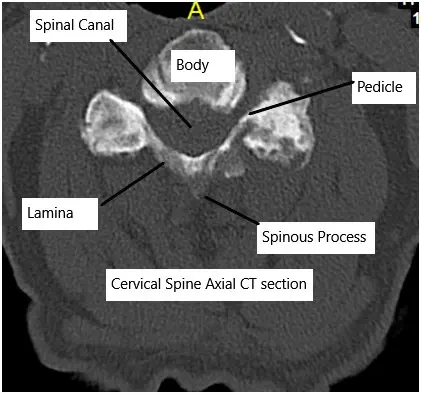

Cervical CT scan showing axial section.

The cervical spine has seven vertebrae separated by discs that act as cushions. Each disc has a tough outer ring (annulus fibrosus) and a gel-like center (nucleus pulposus). These structures allow flexibility and absorb shock. Nerves travel through openings in the vertebrae to the arms and upper body.

- CT scans to detail bone changes or calcified ligaments